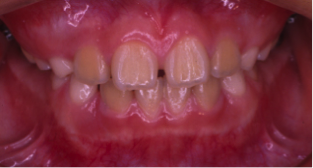

治療前

治療後

奥の歯が倒れて狭くなっている台形の歯列を広げて歯を起こす治療で、奥の歯が見えるようになるUの字型に治しました。

上の歯下の歯、それぞれ2本づつ第一小臼歯を抜歯した治療となりました。

歯を見せて笑えるようになり喜んでもらいました。